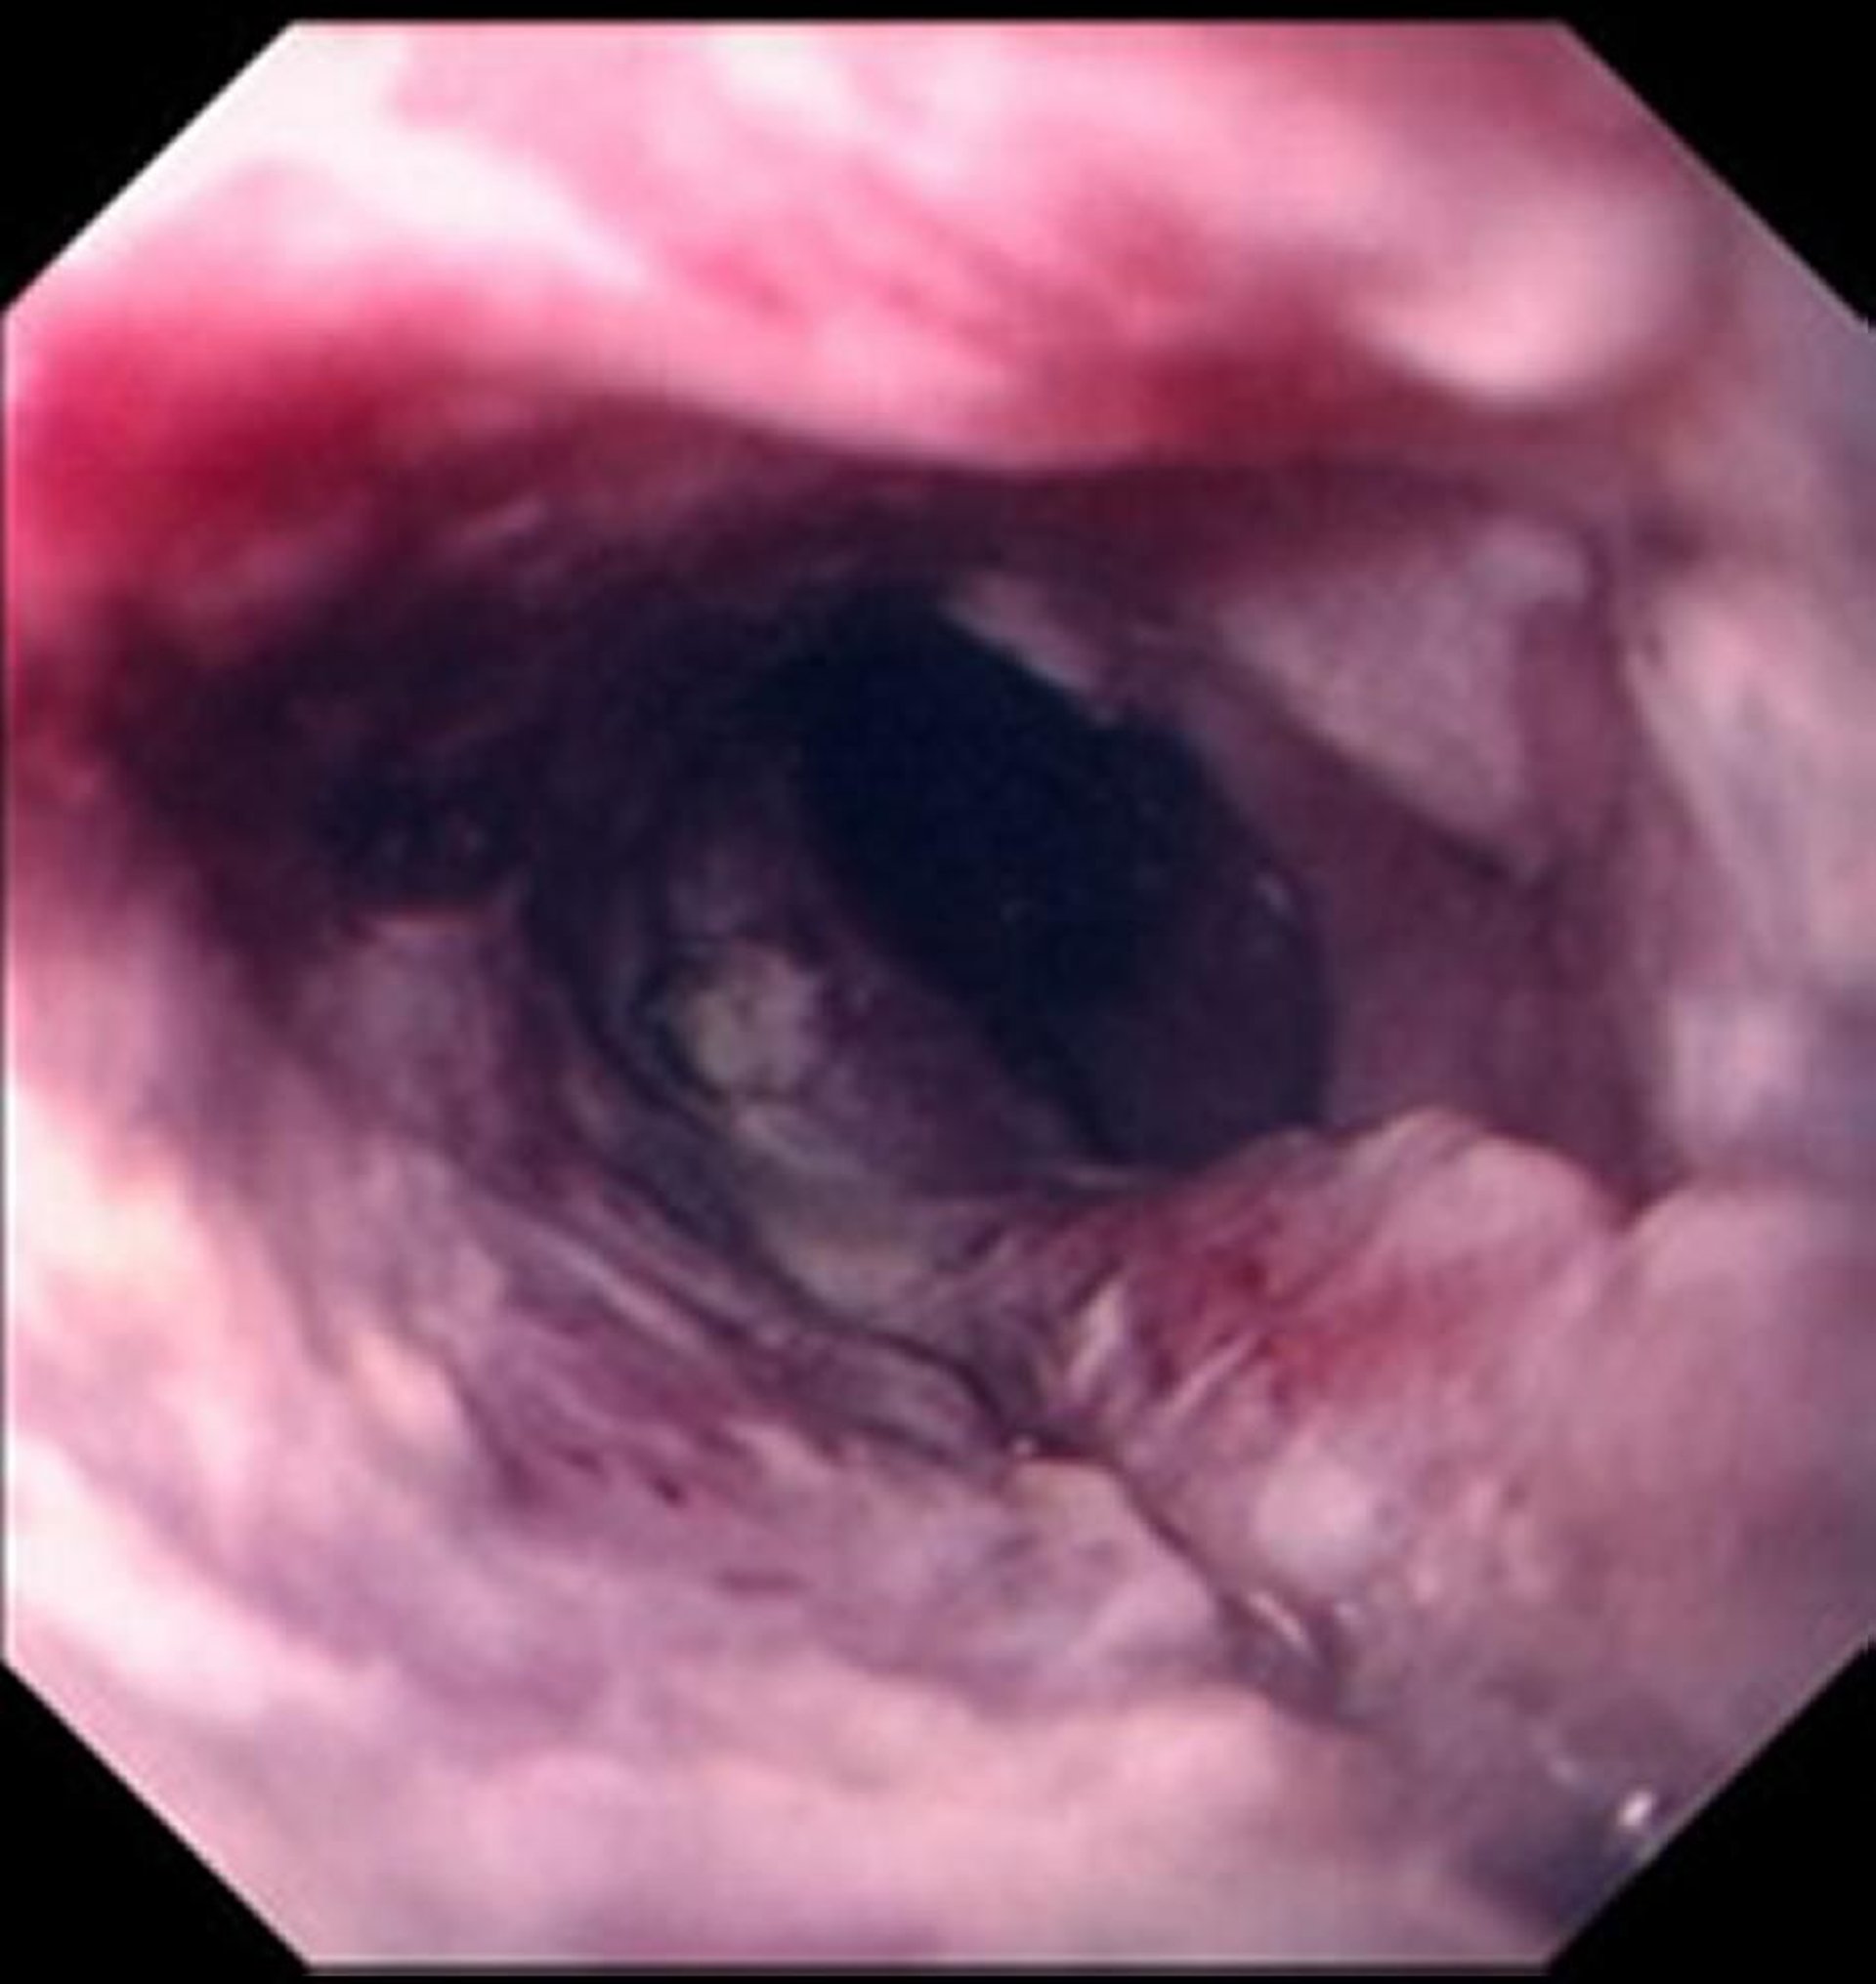

Carcinoma espinocelular do esôfago

O carcinoma espinocelular do esôfago tipicamente se manifesta como uma massa ulcerada e irregular comprometendo a luz do esôfago.

Images provided by David M. Martin, MD.